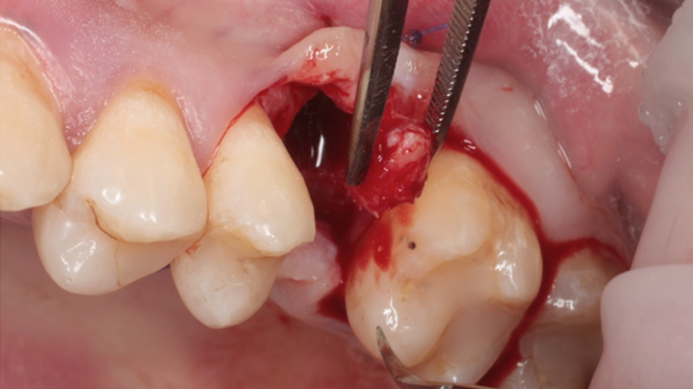

“Thin ridge expansion with minimally invasive surgery!

Use SmarThor & AnyRidge to place a wider diameter implant with minimal drilling after ridge splitting, even in thin ridge under 2mm! “

Clinical case: Ridge splitting technique using SmarThor + AnyRidge as expander

- Courtesy of Dr.Kwang-Bum Park, Korea -

Keywords

AnyRidge, ridge splitting, GBR, Dr. Kwang-Bum Park, mandibular posterior, SmartThor, Mega-Oss, thin ridge, bone regeneration

Products:

AnyRidge implant system. SmarThor, Mega-Oss